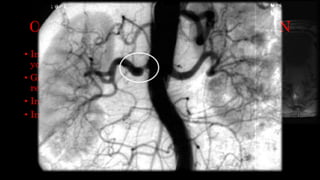

• Intraarteriales: estudios angiograficos con contrastes

yodados.

• Gadolinio con CO2 en pacientes alérgicos con insuficiencia

renal.

OTRAS VIAS DEADMINISTRACION • Intraarteriales: estudios angiograficos con contrastes yodados. • Gadolinio con CO2 en pacientes alérgicos con insuficiencia renal. • Intraarticulares: contraste yodado o gadolinio. • Intracanaliculares: Sialografía o cistografía.